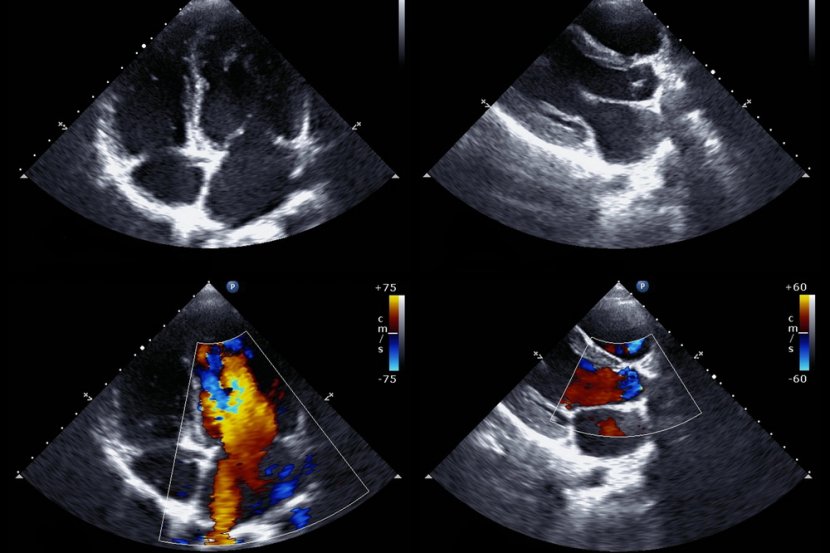

Kongenitalna bolest srca (CHD) ili oboljevanje od hronične srčane bolesti je stanje srčanih abnormalnosti i najčešća je urođena mana. Širom sveta preporučuje se fetalni ultrazvučni pregled, uključujući 5 pregleda srca koji bi zajedno mogli da otkriju 90 odsto ove složene bolesti srca. Međutim, u praksi se pokazalo da je osetljivost na ovakvu vrsta pregleda dosta niska, samo 30 procenata. Tu sliku promenio je američki tim naučnika koji je kreirao softverski metod dijagnostike koji je 100 odsto precizan u razlikovanju normalnog od abnormalnog srca.

Koristeći 107.823 snimaka sa 1.326 retrospektivnih ehokardiograma i pregleda fetusa od 18 do 24 nedelje, istraživački tim ustanovio je ansambl neuronskih mreža kako bi identifikovali preporučene srčane preglede i  napravili razliku između normalnog srca i složene kongenitalne bolesti srca. Takođe su koristili modele segmentacije za izračunavanje standardnih fetalnih kardiotorakalnih merenja. U testiranoj grupi od 4.108 fetalnih pregleda, novi softverski model pregleda srca postigao je ostetljivost od 95 odsto, specifičnost od 96 procenata i bio 100 odsto precizan u razlikovanju normalnog od abnormalnog srca.